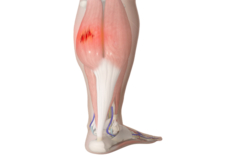

Medial Gastrocnemius Strain

A medial gastrocnemius strain (MGS), also sometimes called “tennis leg”, is an injury to the calf muscle in the back of the leg. It occurs when the calf muscle is stretched too far resulting in a partial or total tear or rupture within the muscle.